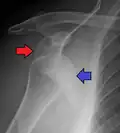

A Hill–Sachs lesion is an impaction of the head of the humerus left by the glenoid rim during dislocation.[6] Hill-Sachs deformities occur in 35–40% of anterior dislocations. They can be seen on a front-facing X-ray when the arm is in internal rotation.[11] Bankart lesions are disruptions of the glenoid labrum with or without an avulsion of bone fragment.[12]

Anterior dislocation of the right shoulder. AP X ray -

Anterior dislocation of the right shoulder. Y view X ray.